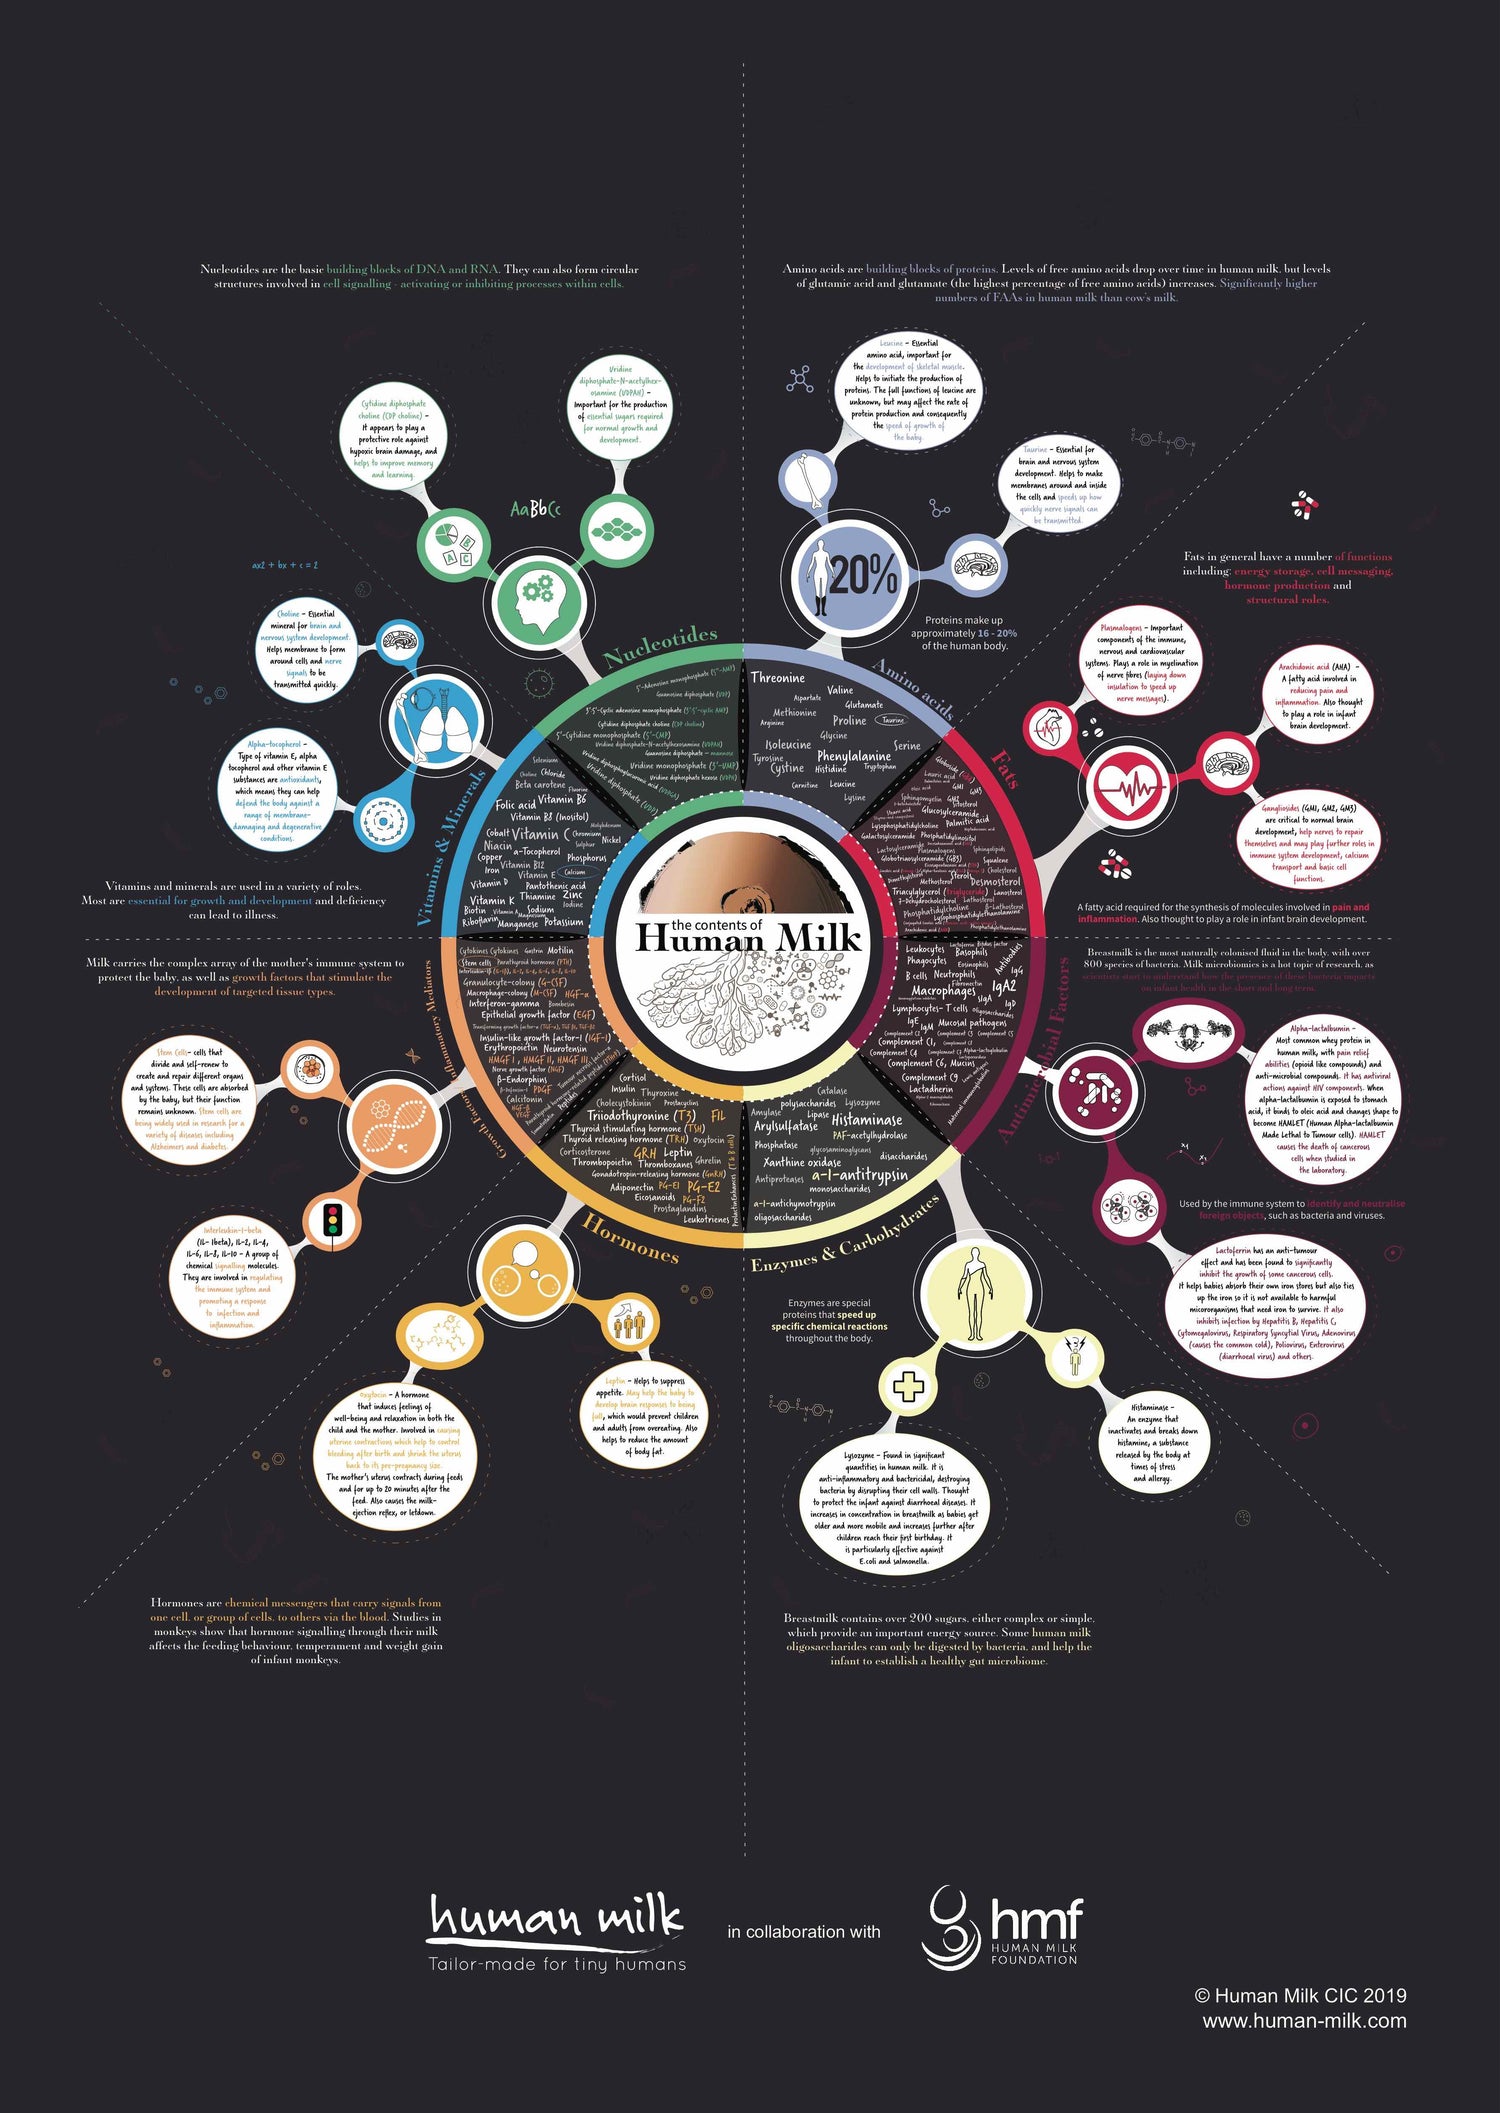

Breastmilk contains thousands of ingredients and is constantly adapting to your child’s needs, age, health, development, to the time of day or night, and even to the weather.

Art & Science Resources

Posters and postcards full of remarkable knowledge about human milk and breastfeeding.

The remarkable science of human milk

Did you know that you can download our science resources for digital and print use, completely free of charge?

Join the thousands of healthcare settings using our resources in 35+ countries to support new parents.